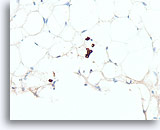

Invasief lobulair carcinoom, Borst FNA, Celblok.

Dunne strengen met lobulaire carcinoomcellen infiltreren het vetweefsel.

40X

Invasief lobulair carcinoom, Borst FNA, Celblok.

Dunne strengen met lobulaire carcinoomcellen infiltreren het vetweefsel.

40X